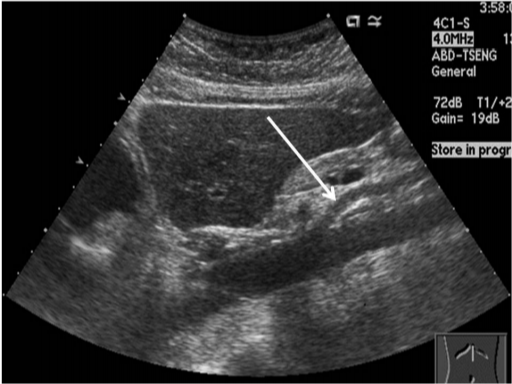

담낭 및 담도계 질환

- 담낭결석(담석증): 담낭 내 결석 존재 여부, 크기, 위치 확인

- 담낭염: 담낭 벽의 두께 증가, 액체 저류 관찰 가능

- 담도 폐쇄 및 담관암: 담관 확장 여부 및 폐쇄 병변 확인